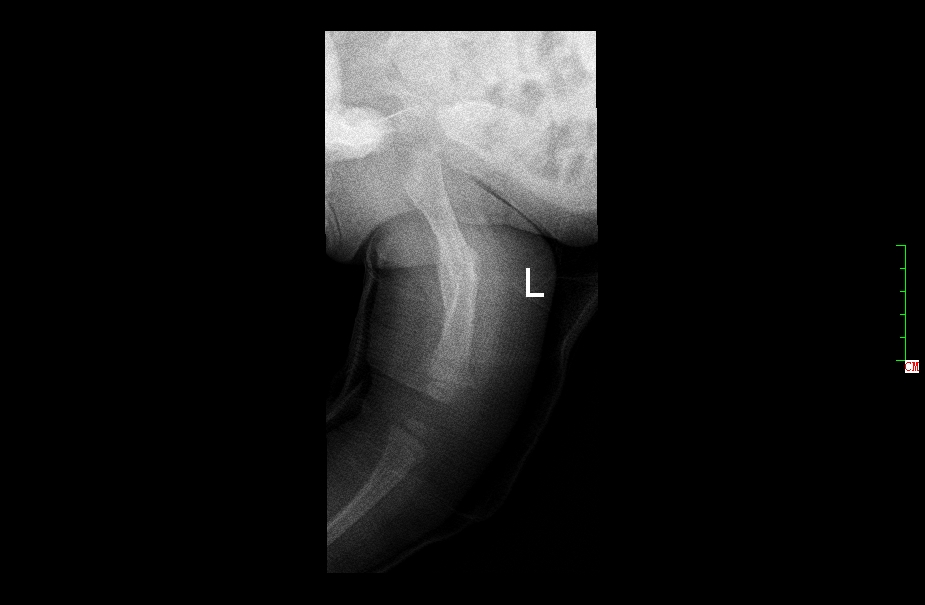

1年后复查正位片,已完全愈合,自行矫形至正常